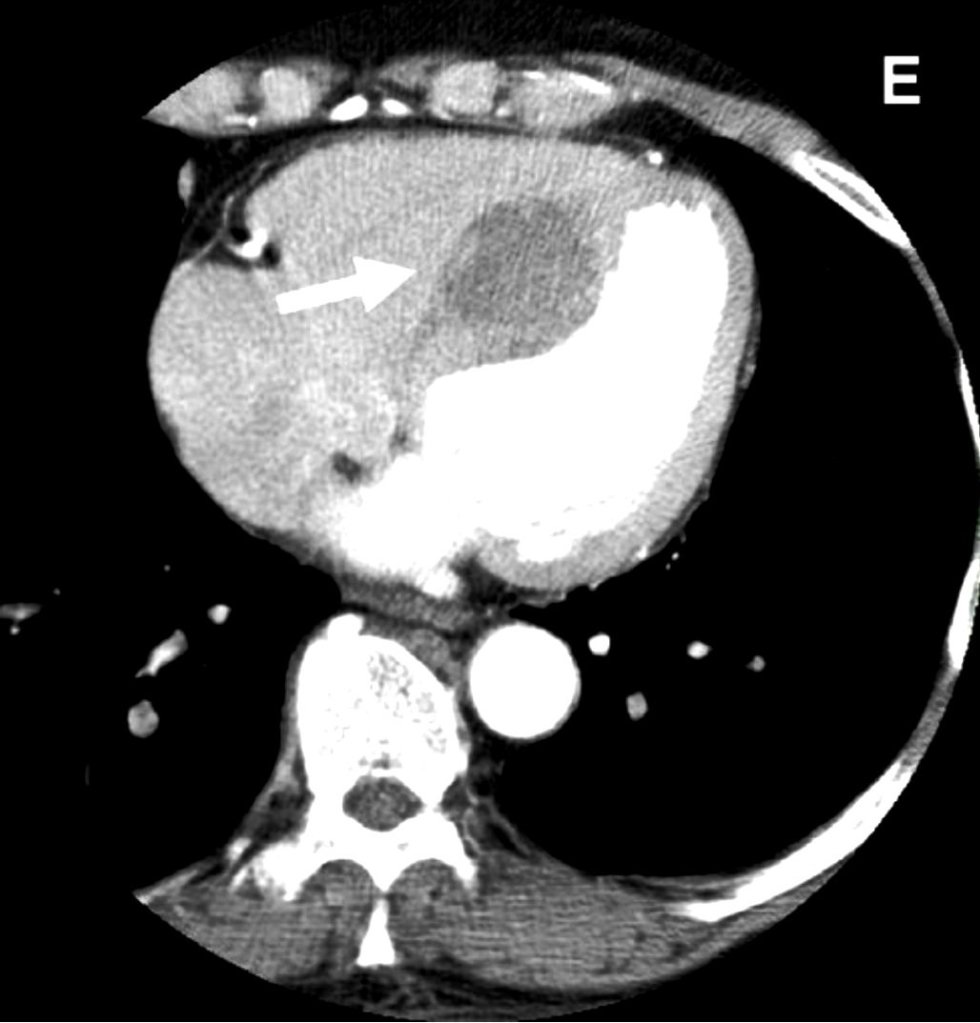

What is the lesion?

It looks like an  Intracardiac tumor, a myxoma ? a variant of HCM ?  Is it a hydatid cyst, ?

No it’s not. I can give one clue. This is a man-made condition.

Oh ok, did this happen inside the cath lab ?

Yes, you got it, right. But need a diagnosis.

Can you give me one more clue?

This patient was undergoing PCI for chronic total occlusion.

So, it must be a complication. Then I need to know the list of complications during CTO PCI.

Yes, but you may not find this one in the conventional list. Let me come out with the answer.

Answer

It is a huge septal hematoma due rupture of vulnerable septal collateral during retrograde wiring for opening LAD CTO.It usually occurs due to o prolonged procedures and hardware-related injury. Thanks to the authors from Taiwan to post this case report. (Image Courtesy Lin & Wu 2005 Ref 1)

Lessons from this case report (Not meant to offend anyone )

This case gives us some important lessons to be learned. One of my senior colleagues used to say, opening a CTO is ok, but using a retrograde approach with aggressive deploying of hardware within the last remaining lifeline provided by the donor coronary artery is a culpable coronary crime unless it is a life-saving procedure.

The often used term “septal surfing” adds an “adventure sport feel” to our youngsters posing as an interventional challenge and amplifying the potential injury. The fact that epicardial collaterals have a larger caliber, but the temptation to cross it, is significantly suppressed (or even forbidden) due to the risk of tamponade. However, this doesn’t in any way give us the freedom to toy with septal collaterals. Proliferating hardware  (Innovative though ) is also an issue. It is true, technological input is a pillar for the growth of science. However, it is a sad fact, many of us are compelled to learn risky, unscrutinized tricks exclusively from academically unbaked industry guys, rather than from mainstream literature.

Final message

“No procedure … no complication”

I could recall, one of my colleagues displayed this caption as the last slide in a cath lab workshop,  after a talk on How to avoid complications in the cath lab.

Very true. But, CTO by itself never belongs to a malignant subset of CAD, as some sections of the cardiology community would want us to believe. CTOs do need an intervention, only as a  life-saving /0r severe symptom-relieving procedure. Most of them aren’t.  They present with stable angina because of extensive collaterals.  Unfortunately, instead of respecting this, many of us are asked to close these channels and try to maintain antegrade flow. The irony is, to open the CTO we may end up sacrificing these life-saving channels.

Reference

1.Lin, T.-H., Wu, D.-K., Su, H.-M., Chu, C.-S., Voon, W.-C., Lai, W.-T., & Sheu, S.-H. (2006). Septum hematoma: A complication of retrograde wiring in chronic total occlusion. International Journal of Cardiology, 113(2), E64–E66. doi:10.1016/j.ijcard.2006.04.032